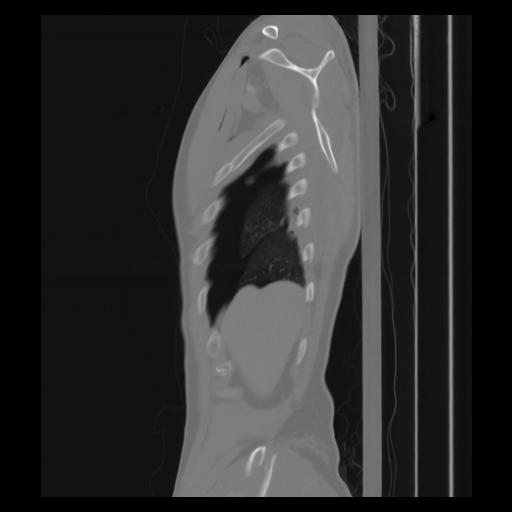

30 CUERPO,CE,Sagittal,3.000,CUERPO,Sagittal,